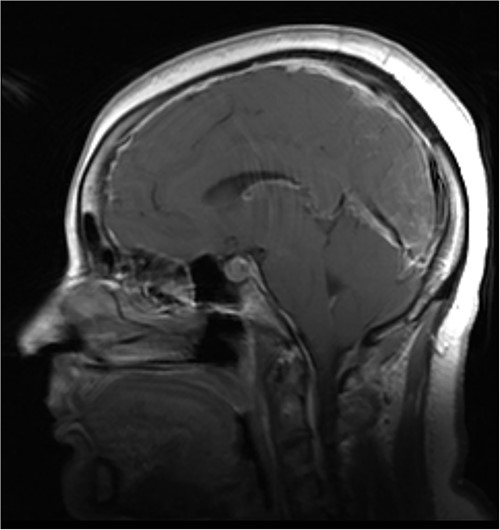

MRI of the brain (see Fig. 1) revealed features of low intracranial pressure. An MRI of the spine (see Fig. 2) revealed focal thoracic herniation of the ventral cord through the thecal sac with CSF signal in the anterior epidural space. No cord signal abnormality was demonstrated. Neurological examination was unremarkable with no numbness or weakness of the lower limbs.

Illustrative sagittal gadolinium enhanced T1 MRI of the brain demonstrating the sequalae of intracranial hypotension, the likes of which may be precipitated by a ventral spinal dural defect; there is smooth pachymeningeal enhancement, partial effacement of the cortical sulci, sagging cerebellar tonsils, a full appearing pituitary gland and slight prominence of the straight sinus; illustrative sagittal gadolinium enhanced T1 MRI of the brain, demonstrating the sequalae of intracranial hypotension, the likes of which may be precipitated by a ventral spinal dural defect; case courtesy of Behrang Amini, from the case rID: 36019 (https://radiopaedia.org/cases/36019?lang=gb)